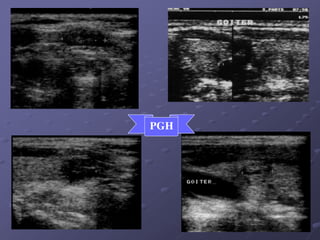

PGH

 PG ñôn haït hay ña haït: Haït coù caáu truùc echo raát

keùm so vôùi chuû moâ giaùp. Giôùi haïn roõ hay khoâng ro,õ

keøm theo tình traïng voâi hoùùa (to) hay hoùa nang trong